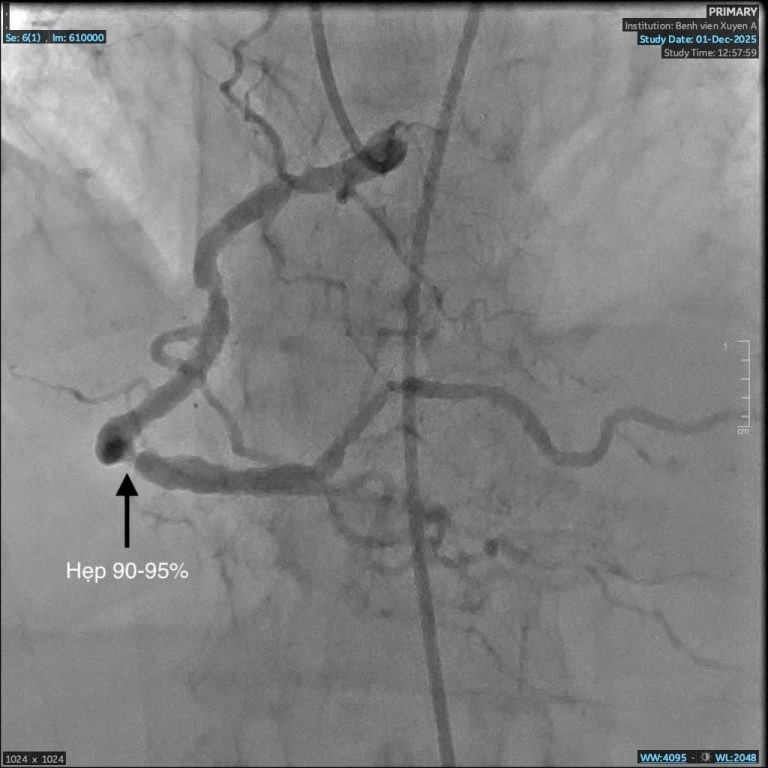

Mạch máu hẹp trước can thiệp - Ảnh BVCC

Mạch máu trước can thiệp hẹp đến 95% - Ảnh BVCC

Kết quả chụp động mạch vành phát hiện bà C. bị hẹp nặng ba nhánh mạch vành, rơi vào nguy kịch nhồi máu cơ tim. Đây là nguyên nhân chính khiến bà khó thở, đau nặng ngực.